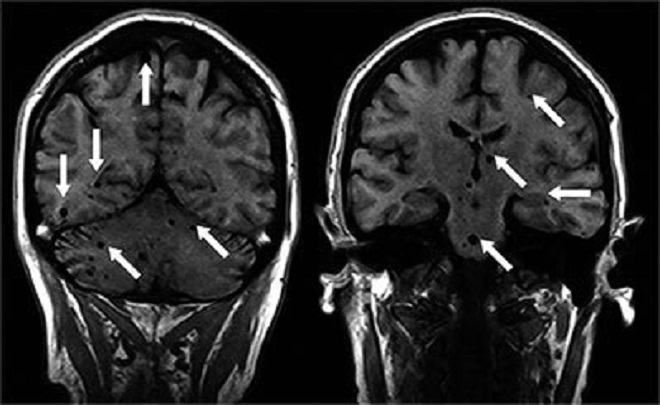

Установить присутствие паразитов в головном мозге человека можно при помощи компьютерной томографии и МРТ.

Диагностика нейроцистицеркоза

Установить диагноз больного нейроцистицеркозом довольно сложно. На первоначальных стадиях заболевание протекает бессимптомно. Для установления правильного диагноза используют рентген, МРТ и КТ. Свидетельствовать о наличии заболевания может повышенный уровень эозинофилов, положительный результат РСК.